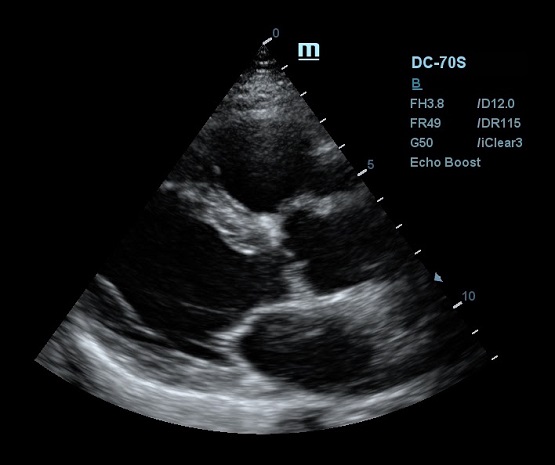

Благодаря постоянным инновациям, компания Mindray внедрила технологию iClear (адаптивная обработка изображений). Спекл - артефакт визуализации в виде акустического пятна - был препятствием для дифференциации структуры исследуемой ткани. iClear реализует агрессивное подавление спекл-паттернов, позволяя четко визуализировать анатомическую структуру на ультразвуковых изображениях. За счет уменьшения спекл-шума достигается лучшая дифференцировка тканей. Повышается контрастное разрешение без ущерба для пространственного разрешения. Уровень подавления спеклов можно выбрать под свои задачи, достаточно нажать кнопку или повернуть ручку, остальное сделает программный алгоритм.

Другим важным нововведением в постобработке ультразвукового изображения является система EchoBoost. Ткани миокарда отражают различные по интенсивности ультразвуковые волны, и при обработке их одним потоком качество изображение оставляет желать лучшего. Технология EchoBoost позволяет прибору производить анализ эхо-сигналов разной интенсивности индивидуально, создавая затем четкую картинку.

Прибор также обрабатывает каждую область исследуемого региона отдельно, учитывая особенности распространения ультразвуковой волны. В связи с тем, что ультразвуковая система рассматривает низкоинтесивные колебания отдельно, имеется возможность усилить слабое эхо и отделить его от шума. Таким образом сонограмма становится более детальной и четкой, что очень критично в эхокардиографии.